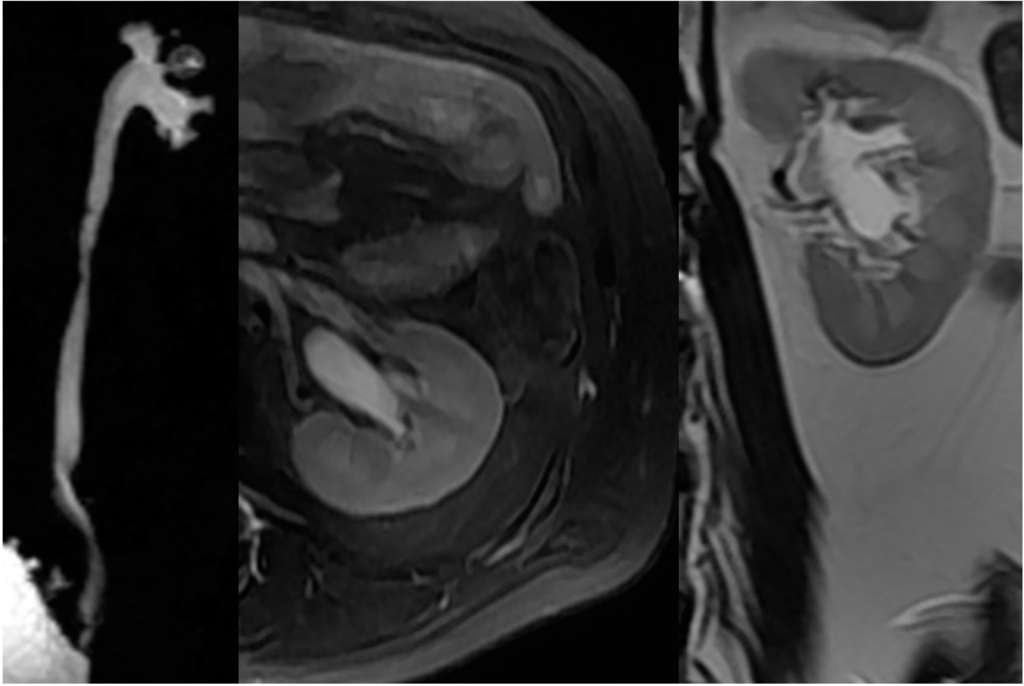

2.4. Upper Urinary Tract Imaging

2.4.1. Upper Urinary Tract Dilation (UUTD)

2.4.2. Vesicoureteral Reflux

- Liao, L.M.; Zhang, F.; Chen, G. New grading system for upper urinary tract dilation using magnetic resonance urography in patients with neurogenic bladder. BMC Urol. 2014, 14, 38–45. [Google Scholar] [CrossRef] [PubMed]